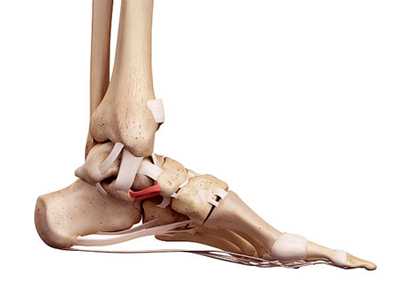

Рис. 3. Связки сустава Шопара:

TN - тыльная таранно-ладьевидная связка.

DDC - тыльная пяточно-кубовидная связка (Tafur M.)